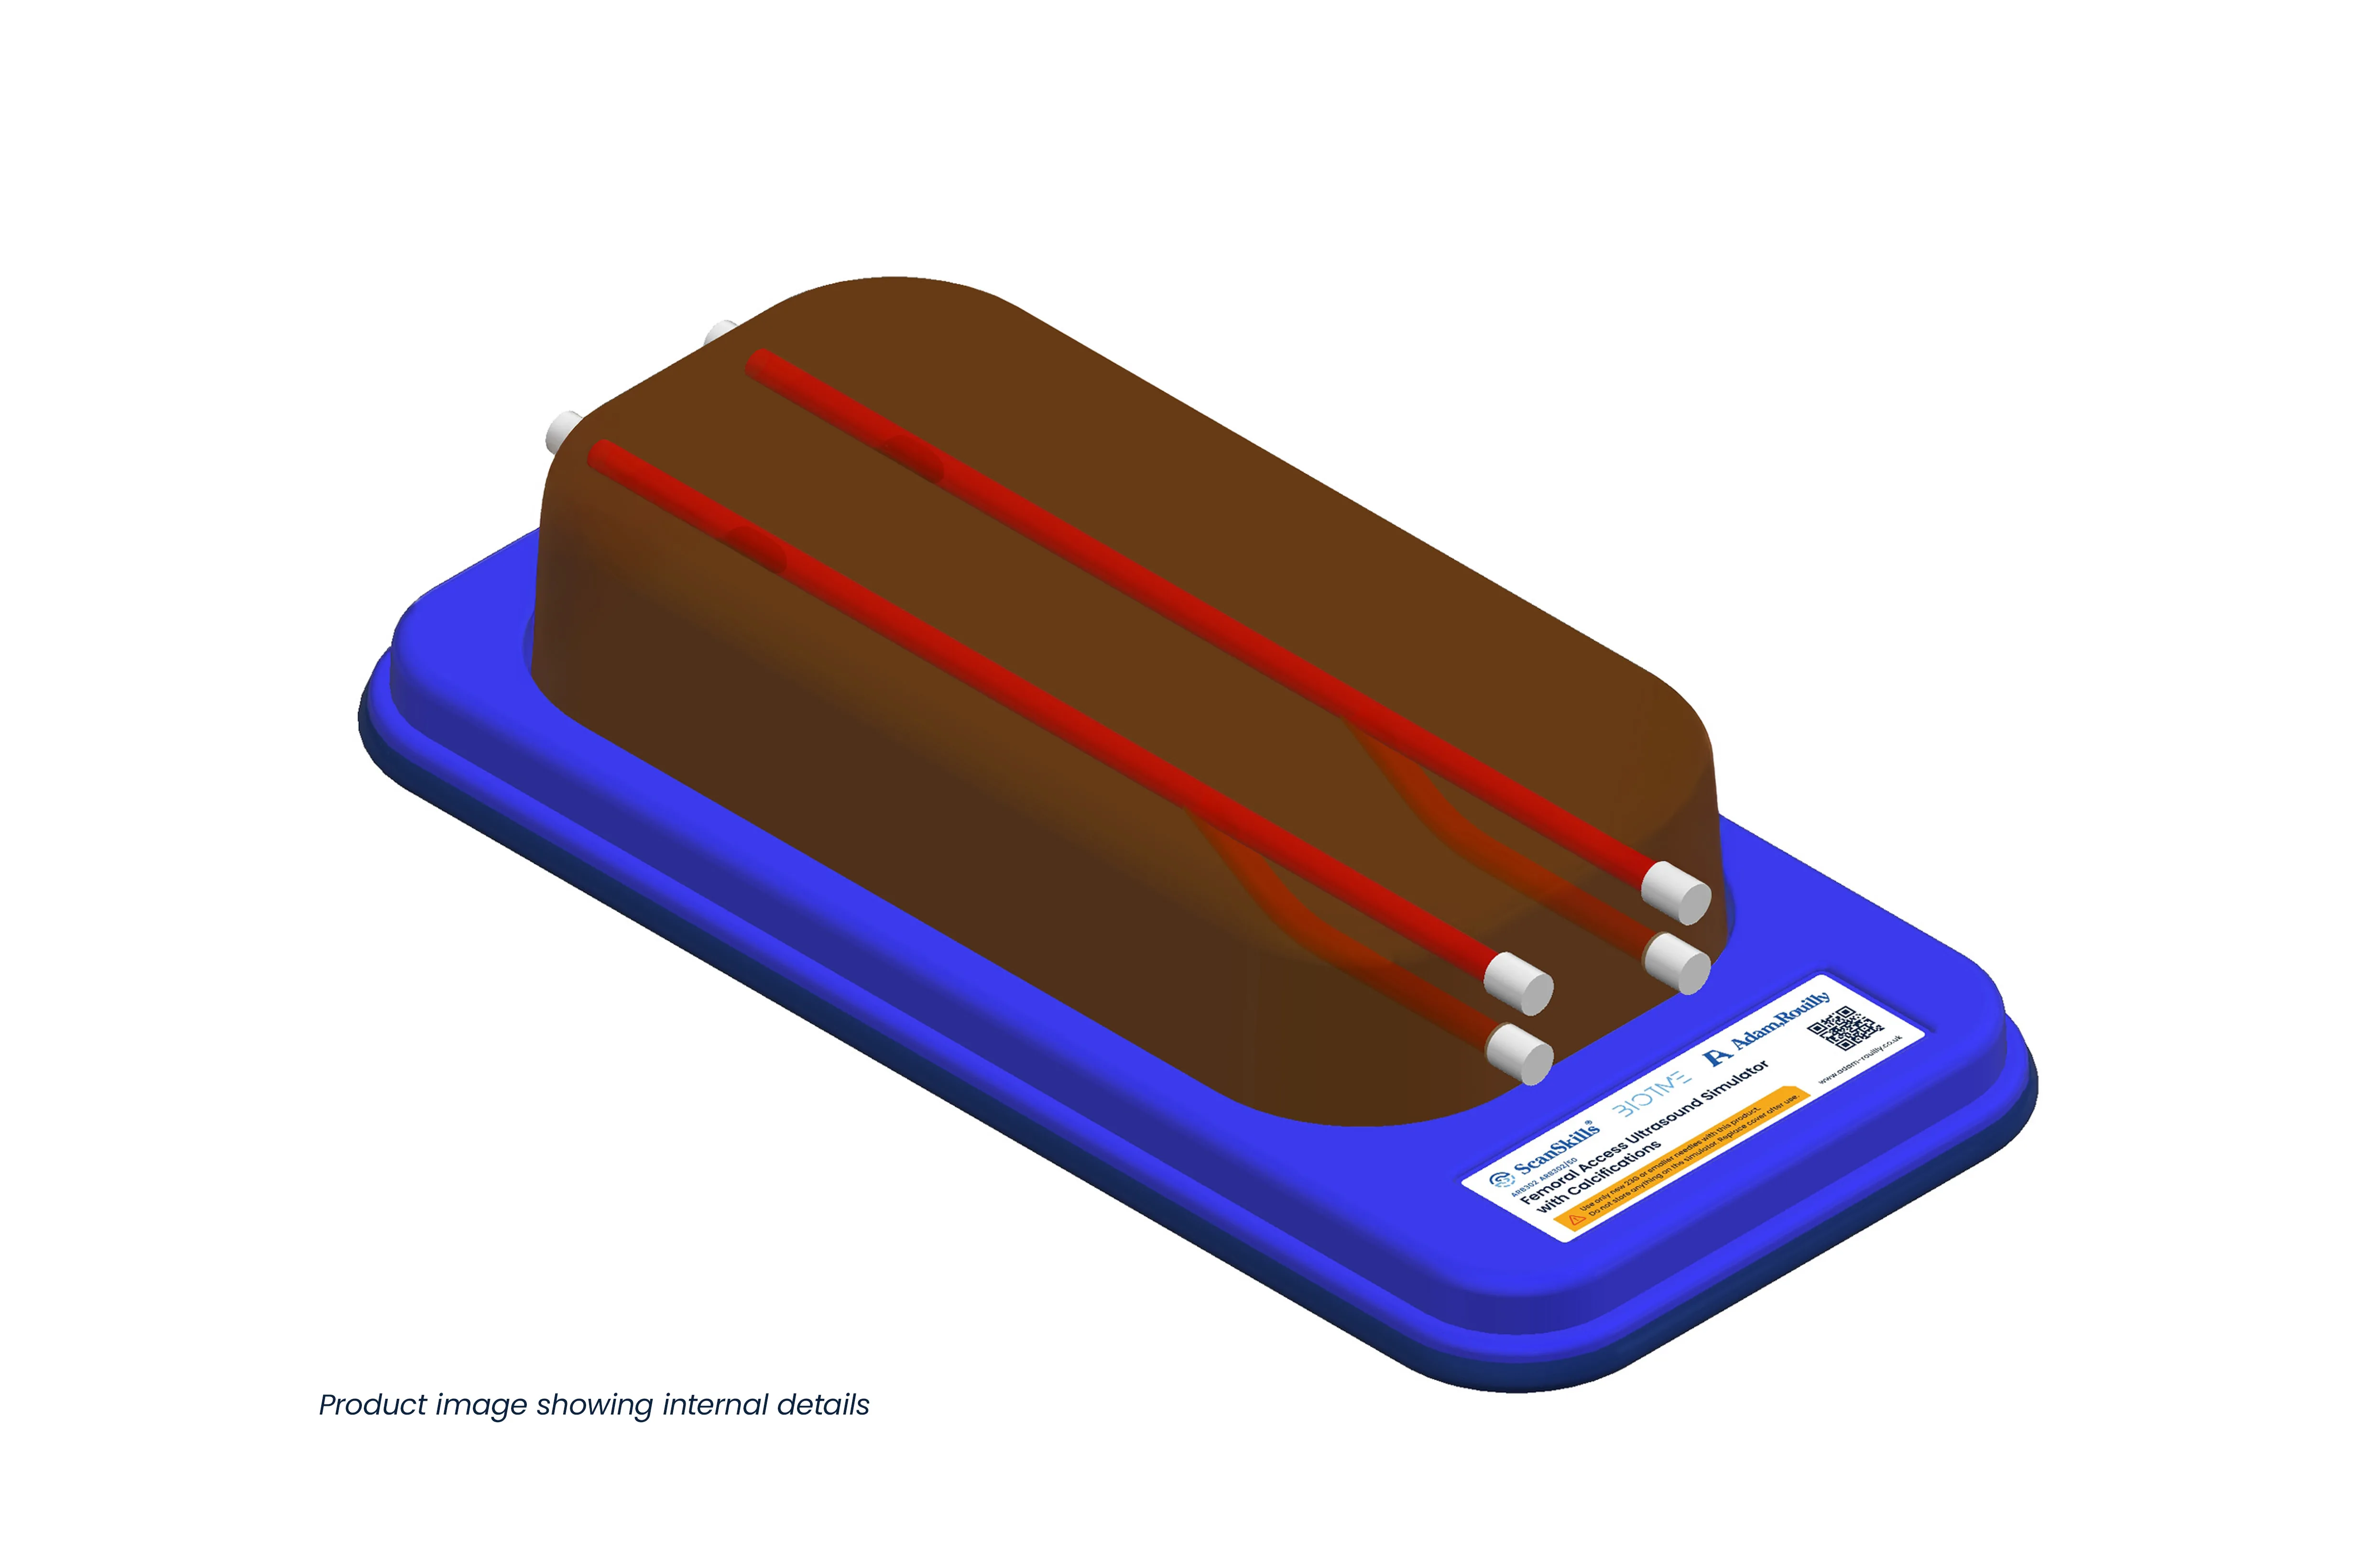

Designed for femoral vascular access training, this simulator features two vertically branched veins (approx. 8 mm diameter, 20 mm deep) with simulated calcifications. Lifelike echogenic material closely mimics human tissue, enabling realistic ultrasound-guided practice, probe control, and anatomy recognition in a safe, repeatable environment for both trainees and experienced clinicians.

- For femoral access with two vertically branched blood vessels with simulated calcifications

- Veins of diameters approximately 8 mm, located 20 mm below the surface of the simulator for vascular access

- Tubeless veins occlude when pressed either by hand or ultrasound probe

- Vein occlusion is visible under ultrasound

- Veins pre-filled with mock blood. Easily refill with our ARB600 Mock Blood Kit